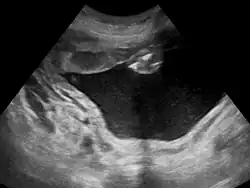

![]() Wielowodzie widoczne w badaniu USG | |

Wielowodzie (łac. polyhydramnion, ang. polyhydroamniosis) – nadmierna ilość płynu owodniowego w czasie ciąży. Wielowodzie rozpoznaje się, gdy ilość płynu w III trymestrze ciąży wynosi ponad 2000 ml albo gdy wskaźnik AFI wynosi >25[1].